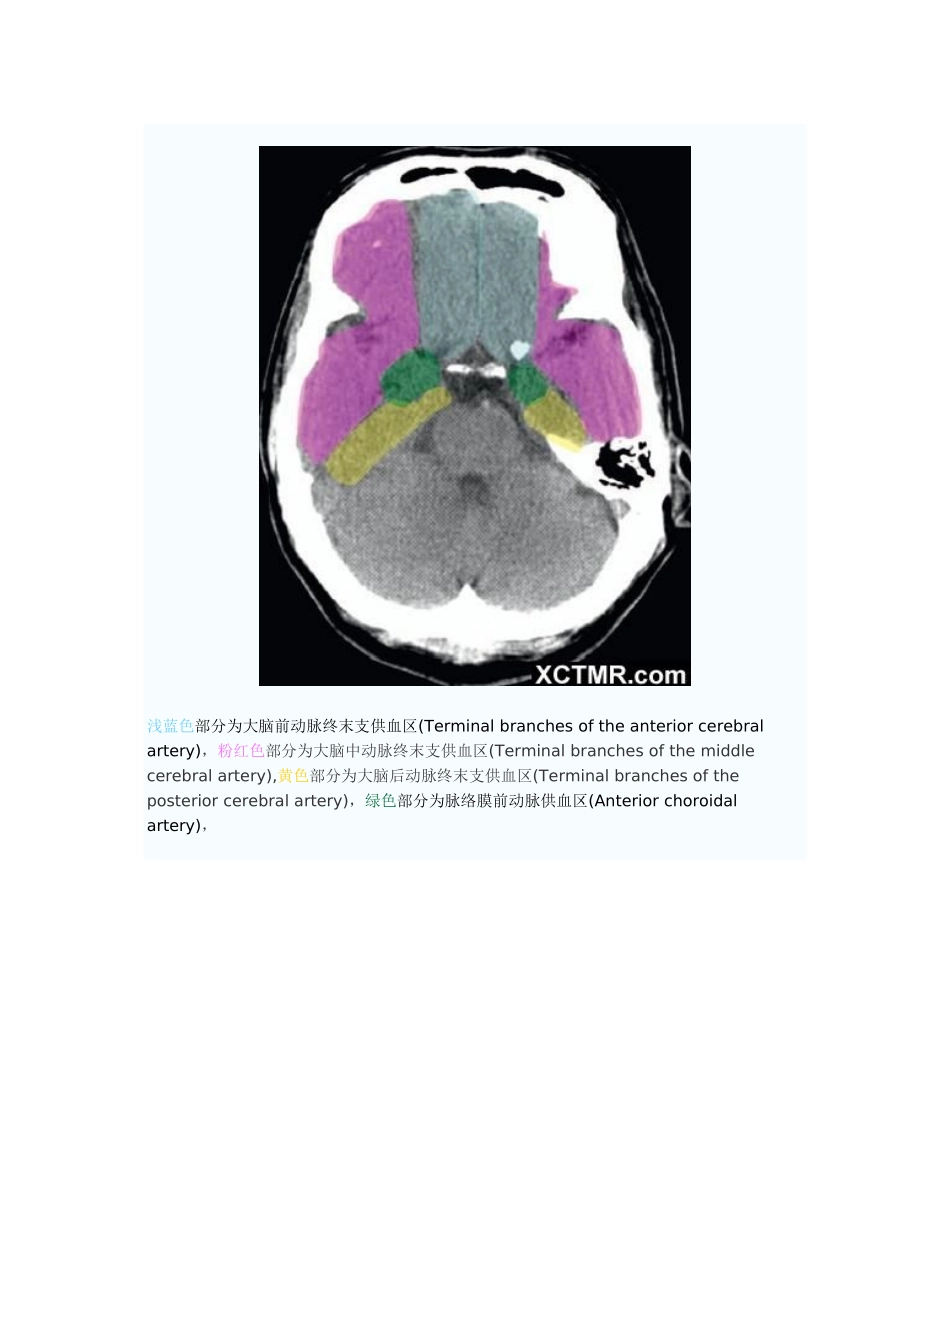

大脑动脉血管供血分区CT解剖(图文)来源:作者:【复制分享】【讨论-纠错】【举报】浅蓝色部分为大脑前动脉终末支供血区(Terminalbranchesoftheanteriorcerebralartery),粉红色部分为大脑中动脉终末支供血区(Terminalbranchesofthemiddlecerebralartery),黄色部分为大脑后动脉终末支供血区(Terminalbranchesoftheposteriorcerebralartery)浅蓝色部分为大脑前动脉终末支供血区(Terminalbranchesoftheanteriorcerebralartery),粉红色部分为大脑中动脉终末支供血区(Terminalbranchesofthemiddlecerebralartery),黄色部分为大脑后动脉终末支供血区(Terminalbranchesoftheposteriorcerebralartery),绿色部分为脉络膜前动脉供血区(Anteriorchoroidalartery),浅蓝色部分为大脑前动脉终末支供血区(Terminalbranchesoftheanteriorcerebralartery),粉红色部分为大脑中动脉终末支供血区(Terminalbranchesofthemiddlecerebralartery),黄色部分为大脑后动脉终末支供血区(Terminalbranchesoftheposteriorcerebralartery),绿色部分为脉络膜前动脉供血区(Anteriorchoroidalartery),褐色部分为大脑前动脉深穿支供血区(Penetratingbranchesoftheanteriorcerebralartery),枣红色部分为大脑后动脉深穿支及后交通动脉供血区(Penetratingbranchesoftheposteriorcerebralarteryandposteriorcommunicatingartery),浅蓝色部分为大脑前动脉终末支供血区(Terminalbranchesoftheanteriorcerebralartery),粉红色部分为大脑中动脉终末支供血区(Terminalbranchesofthemiddlecerebralartery),黄色部分为大脑后动脉终末支供血区(Terminalbranchesoftheposteriorcerebralartery),绿色部分为脉络膜前动脉供血区(Anteriorchoroidalartery),褐色部分为大脑前动脉深穿支供血区(Penetratingbranchesoftheanteriorcerebralartery),枣红色部分为大脑后动脉深穿支及后交通动脉供血区(Penetratingbranchesoftheposteriorcerebralarteryandposteriorcommunicatingartery),亮红色部分为大脑中动脉深穿支供血(Penetratingbranchesofthemiddlecerebralartery)浅蓝色部分为大脑前动脉终末支供血区(Terminalbranchesoftheanteriorcerebralartery),粉红色部分为大脑中动脉终末支供血区(Terminalbranchesofthemiddlecerebralartery),黄色部分为大脑后动脉终末支供血区(Terminalbranchesoftheposteriorcerebralartery),绿色部分为脉络膜前动脉供血区(Anteriorchoroidalartery),枣红色部分为大脑后动脉深穿支及后交通动脉供血区(Penetratingbranchesoftheposteriorcerebralarteryandposteriorcommunicatingartery),亮红色部分为大脑中动脉深穿支供血(Penetratingbranchesofthemiddlecerebralartery)浅蓝色部分为大脑前动脉终末支供血区(Terminalbranchesoftheanteriorcerebralartery),粉红色部分为大脑中动脉终末支供血区(Terminalbranchesofthemiddlecerebralartery),黄色部分为大脑后动脉终末支供血区(Terminalbranchesoftheposteriorcerebralartery),枣红色部分为大脑后动脉深穿支及后交通动脉供血区(Penetratingbranchesoftheposteriorcerebralarteryandposteriorcommunicatingartery),亮红色部分为大脑中动脉深穿支供血(Penetratingbranchesofthemiddlecerebralartery)浅蓝色部分为大脑前动脉终末支供血区(Terminalbranchesoftheanteriorcerebralartery),粉红色部分为大脑中动脉终末支供血区(Terminalbranchesofthemiddlecerebralartery),黄色部分为大脑后动脉终末支供血区(Terminalbranchesoftheposteriorcerebralartery),浅蓝色部分为大脑前动脉终末支供血区(Terminalbranchesoftheanteriorcerebralartery),粉红色部分为大脑中动脉终末支供血区(Terminalbranchesofthemiddlecerebralartery),黄色部分为大脑后动脉终末支供血区(Terminalbranchesoftheposteriorcerebralartery),浅蓝色部分为大脑前动脉终末支供血区(Terminalbranchesoftheanteriorcerebralartery),粉红色部分为大脑中动脉终末支供血区(Terminalbranchesofthemiddlecerebralartery),黄色部分为大脑后动脉终末支供血区(Terminalbranchesoftheposteriorcerebralartery),浅蓝色部分为大脑前动脉终末支供血区(Terminalbranchesoftheanteriorcerebralartery),粉红色部分为大脑中动脉终末支供血区(Terminalbranchesofthemiddlecerebralartery),浅蓝色部分为大脑前动脉终末支供血区(Terminalbranchesoftheanteriorcerebralartery)